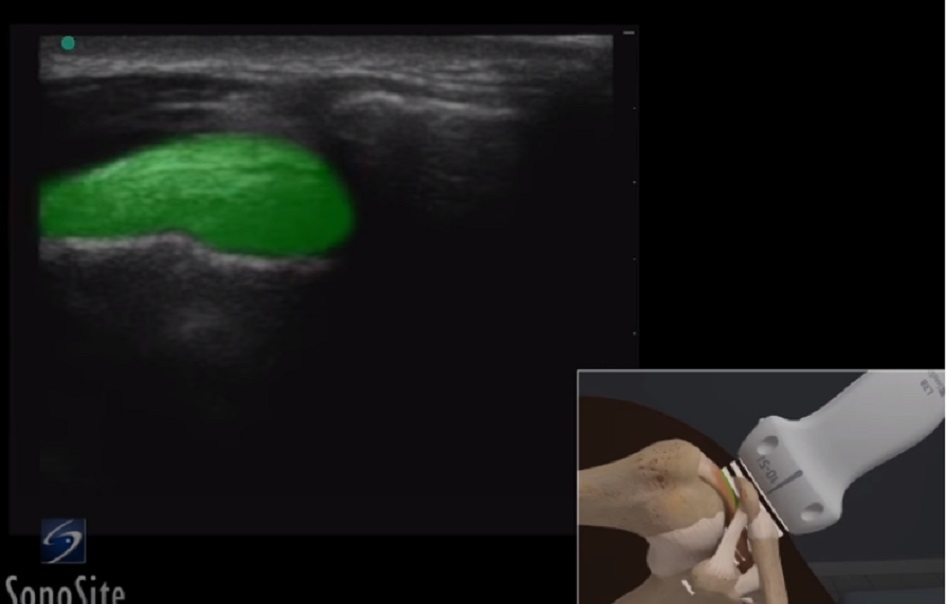

肩肩鎖関節の棘上筋のイメージ

強調表示された領域: 棘上筋腱